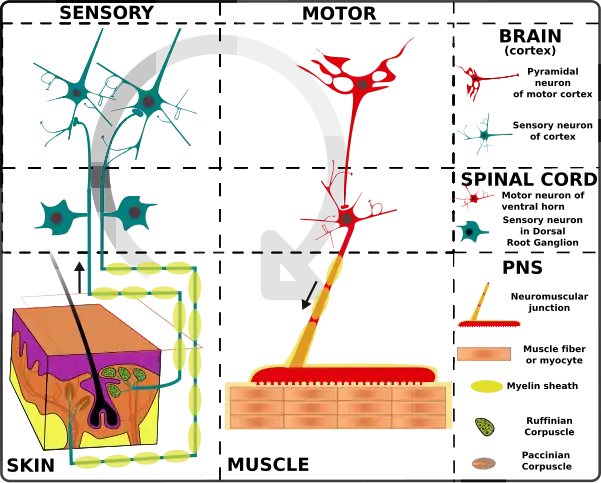

The peripheral nervous system has the ability to regrow cut nerves. Motor axons preferentially reinnervate motor pathways. The tendency of motor axons to reinnervate motor pathways instead of cutaneous pathways is influenced by a number of factors in the PNS system. Some factors include Schwann cell characteristics, neurotrophic factors, and nerve branch size. These factors influence the pathway preference of the motor neuron.[2][3][4] The different nervous systems are illustrated in the image displayed on the right. Preferential motor reinnervation is a tendency that is specifically seen in the peripheral nervous system, which is illustrated in the photos of the bottom of the system shown.